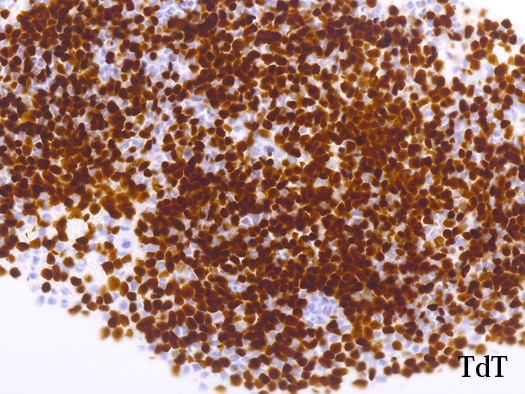

AULはcCD3、MPO、CD19、cCD22、およびCD79a発現を欠き, 通常1つの表面系統マーカー( CD13、CD33、またはCD7など)のみを発現する.CD38またはTdT発現を伴って, CD34およびHLA-DRが陽性になる. *2

blastic cellsは, CD45+, CD34+, CD38+, TdT+, CD7+, HLA-DR+, CD123+. cCD3-, sCD3-(FCM), CD20-, CD19-とCD79a-(?) (plasma cellが陽性でIHCでは判定が難しい), MPO-.

CD3-, CD79aは増加しているplasma cellsが陽性で判定が難しい. CD10-, MPO-. (CD10は画像欠)